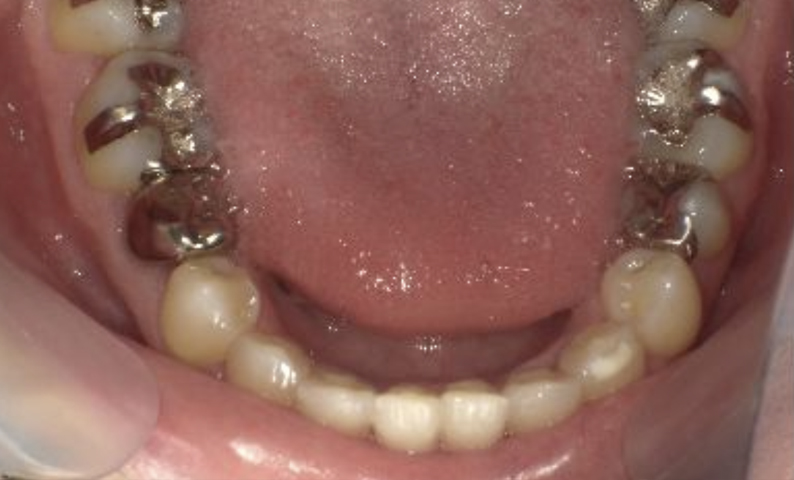

症例_004 下顎だけの部分矯正

治療期間:7ヶ月金額:24万円+税男性前歯のガタガタ下の前歯だけ

| Before | After |